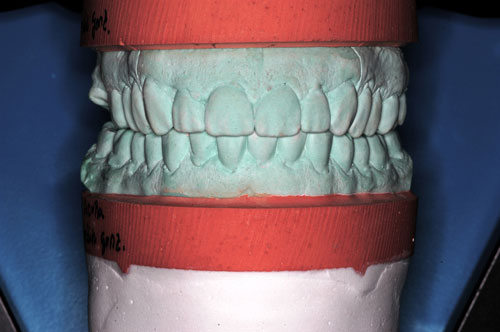

ESTUDIO ESTÁTICO DE LOS MODELOS PREVIOS A LA PRIMERA REHABILITACIÓN APORTADOS POR LA ENFERMA:Modelos Color Blanco

B- ESTUDIO ESTÁTICO DE LOS MODELOS PREVIOS A LA 1ª REHABILITACIÓN APORTADOS POR LA ENFERMA: (La situación oclusal que la enferma tenía antes de que la tocara un dentista (MODELOS COLOR BLANCO)

ESTUDIO ESTÁTICO Y CINEMÁTICO DE LA OCLUSIÓN PRESENTE: Modelos Color Verde

Se realiza un montaje en articulador semi ajustable, mediante la técnica de arco facial convencional para el maxilar superior, y mediante relajación con Laminillas de Long para el inferior. No satisfechos de la certeza del primer montaje, construimos en el un Jig de Lucia que dejamos toda una noche en boca para remontar el inferior al día siguiente a primera hora.

Diferencias entre ambos modelos:

A nivel de segundos molares= 4 mm +

A nivel de primeros molares= 3,50 mm +

A nivel de incisivo central=5,50 mm +